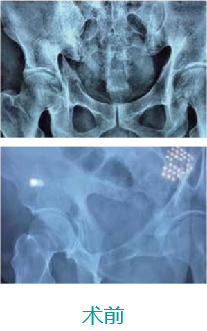

天玑II 辅助骨盆髋臼骨折内牢靠术

基本情形:患者男,,,,,,,,69岁,,,,,,,,骨盆左侧髋臼前后柱损伤